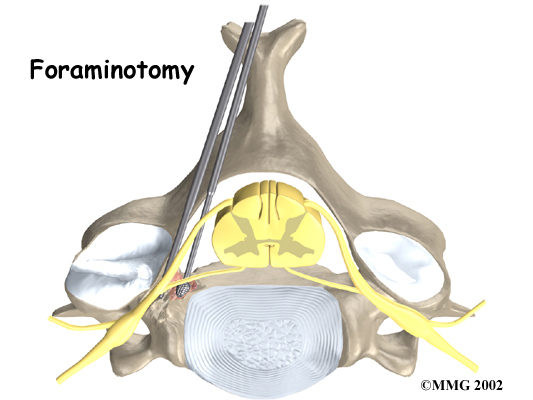

Foraminotomy

A foraminotomy is done to open up the neural foramen and relieve pressure on a spinal nerve root. A foraminotomy may be done because of bone spurs or inflammation.

Foraminotomy

Related Document: FYZICAL Middleburg's Guide to Cervical Foraminotomy